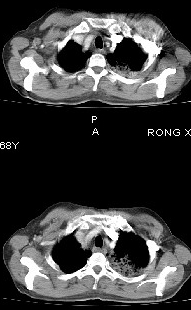

男68岁,反复发热、咳嗽,咯痰1月,曾有咯血史,双肺闻及呼吸音增粗。

左肺上叶尖后段及下叶多发实变阴影,内见支气管充气征,段以上支气管尚通畅,肺门区未见软组织肿块影,结合病人有反复发热病史,首先考虑感染性病变(干酪性肺炎不能排除),建议抗炎治疗后复查或结合纤支镜检查。

左肺上叶尖段及下叶干酪性肺炎可能性大,建议结合临床相关检查.右肺中叶炎症.建议治疗后复查.

该患者在25天前外圆平片见右肺中上肺野大片状影,(治疗不祥,在反复问病史后患者告诉;近一月住在新房内,搞装修),我认为首先考虑是感染,而且过敏性肺炎可能性大。